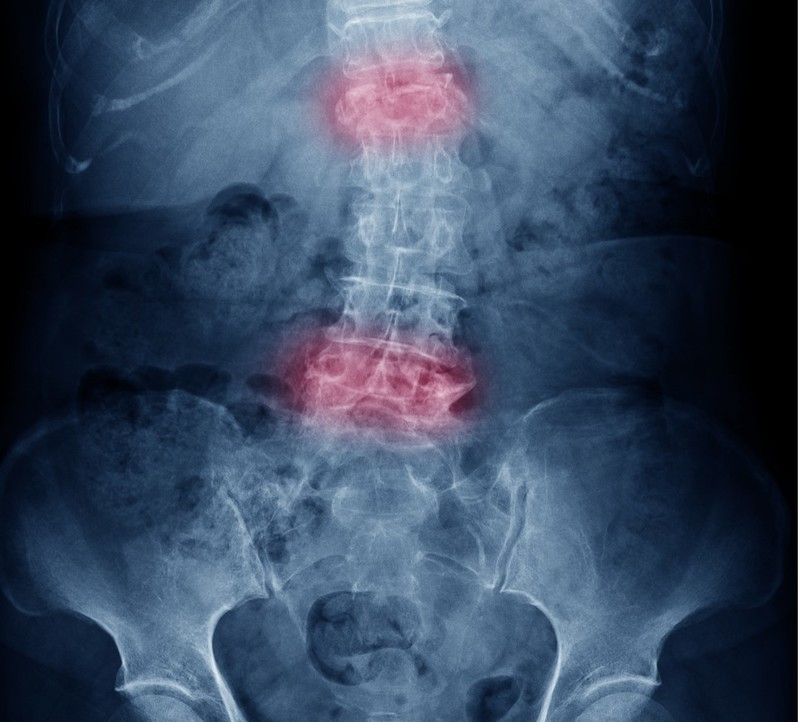

The researchers showed that spinal deformity was a significant risk factor for dislocation and subsequent revision surgery. In a hip replacement, an artificial joint comprising a ball and socket is implanted to replace the natural ball and socket in the pelvis, enabling movement that is typical of the hip joint. While dislocations only occur in about 1 per cent of patients after hip replacement, certain individuals may be at a higher risk.

The overall implant dislocation rate among this cohort was found to be 1.8 per cent. Of this group, 320 patients had spinal disease and deformity as evidenced by imaging scans, and of them, 10 experienced dislocations, suggesting a dislocation rate of 3.1 per cent for high-risk patients, or about three times higher than normal.